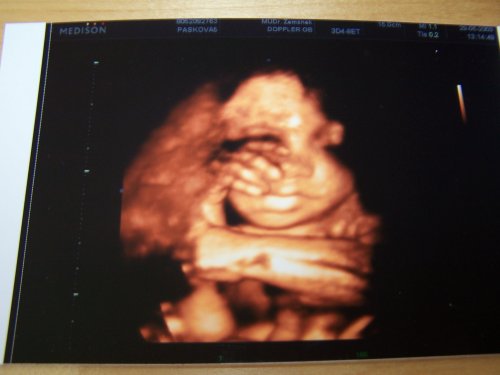

Anetka, naše první štěstíčko 🙂